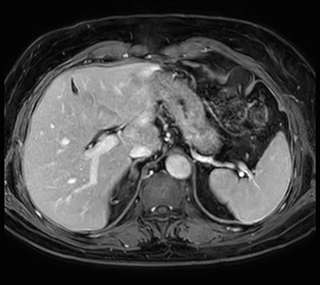

Short breath hold cardiac cine

MCVI Ambition Short breath hold cardiac cine

These are some images of a cardiac cine scan with a short breath-hold time. A high temporal resolution provides a smooth cine, which helps in assessing heart function. Ingenia Ambition.